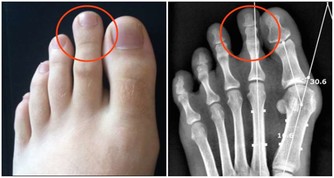

邱大姐,今年64歲。半年前,她出現頭暈、乏力,到醫院檢查,有嚴重的貧血。前段時間病情加重,又到省立醫院就診,發現白細胞、血小板均有減少,進一步檢查確診為「骨髓增生異常綜合症」。

這個病名很專業,可能很多非血液科的醫生都沒聽到過。說直白點,就是患者的造血幹細胞惡性克隆,導致無效造血。白血病,我們通常稱之為血癌,骨髓增生異常綜合征其實也是一種血液腫瘤。這種病預後很差,有30%左右的患者會發展為白血病。